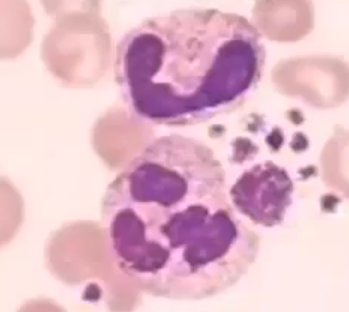

Name

Band neutrophil - Immature

Segmented neutrophil - Mature

Phagocytic - ingest bacteria

Inflammation

Name

Eosinophil

Rare in blood smears (0-5%)

allergen phagocytosis, reduces inflammation from histamines

Name

Basophil

Rarest WBC

slows down blood clotting

Start inflammatory response

Name

Monocyte

largest WBC

larger molecule phagocytic

Pacman

Name

Lymphocyte

Majority nucleus

T cells and B cells